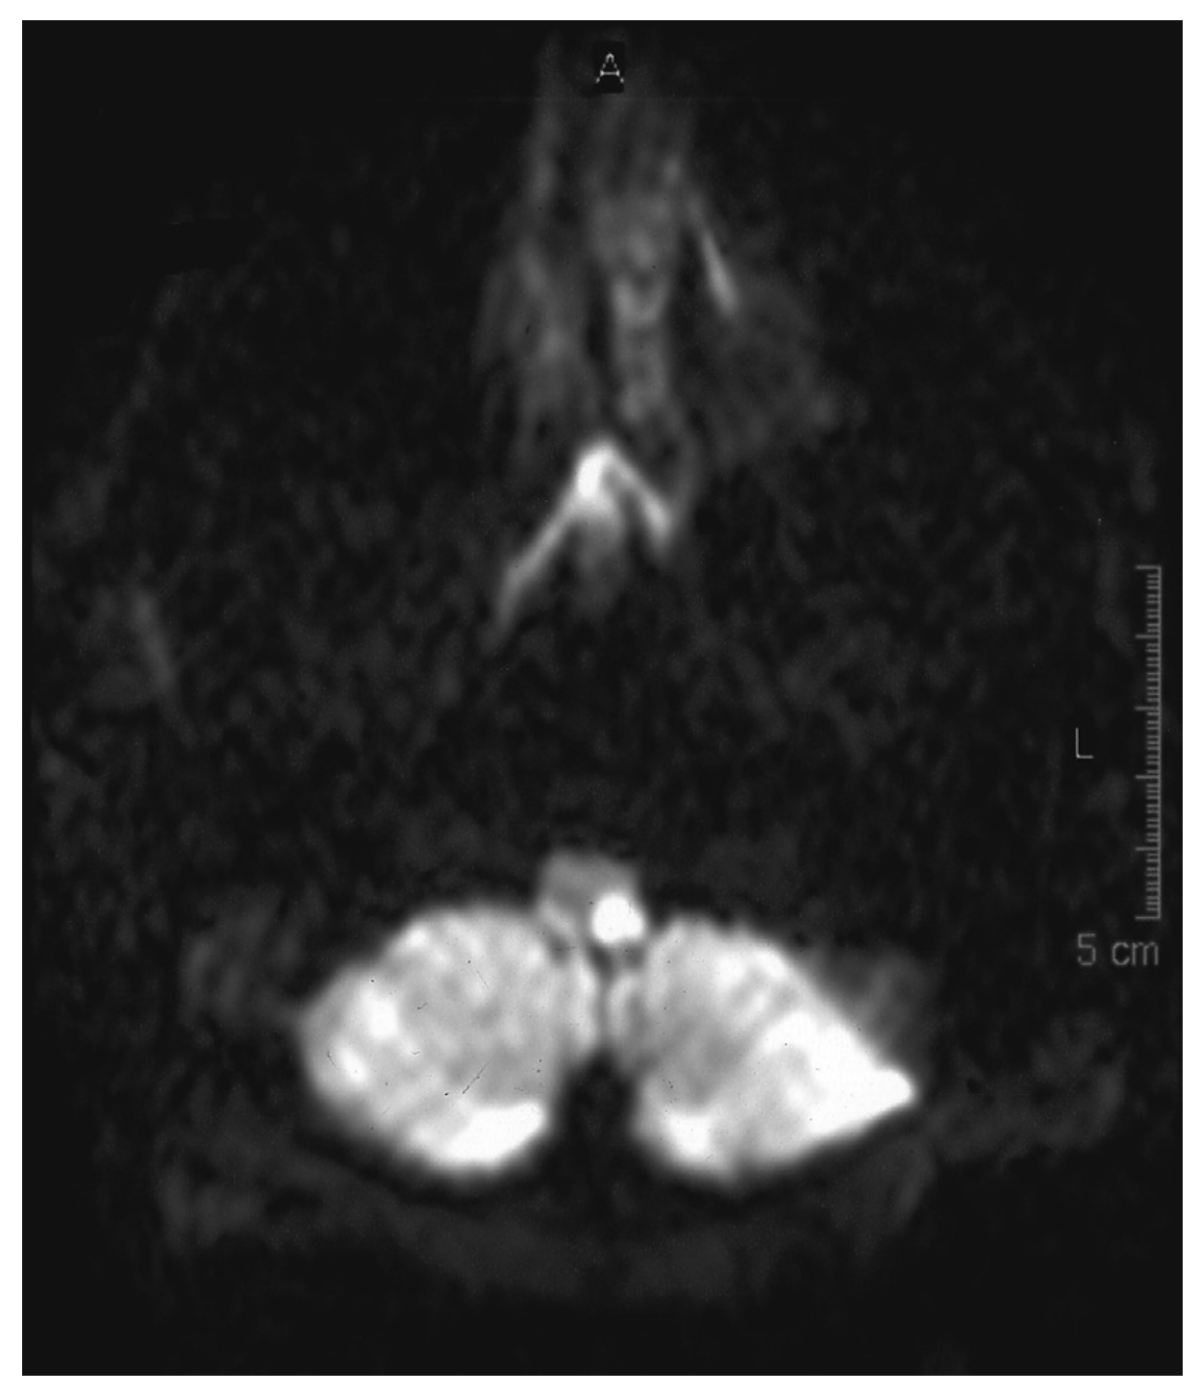

Le diagnostic différentiel principal de la maladie de Ménière est représenté par le schwannome vestibulaire ou les autres processus expansifs de la fosse cérébrale postérieure pouvant potentiellement comprimer le nerf cochléo-vestibulaire. Le schwannome vestibulaire (le terme de neurinome de l'acoustique est incorrect) est une tumeur bénigne développée au dépend des cellules de Schwann du nerf vestibulaire. Il est généralement révélé par une surdité de perception, et parfois par des vertiges. Toute surdité de perception accompagnant des vertiges récurrents doit faire l'objet d'une IRM avec injection de gadolinium centrée sur les conduits auditifs internes, recherchant le schwannome (figure 13.8).

Fig. 13.8.  IRM encéphalique en séquence T1 avec injection de produit de contraste, démontrant une lésion de l'angle ponto-cérébelleux.

IRM encéphalique en séquence T1 avec injection de produit de contraste, démontrant une lésion de l'angle ponto-cérébelleux.

Cette lésion est évocatrice d'un schwannome vestibulaire.

(Source : CEN, 2019.)